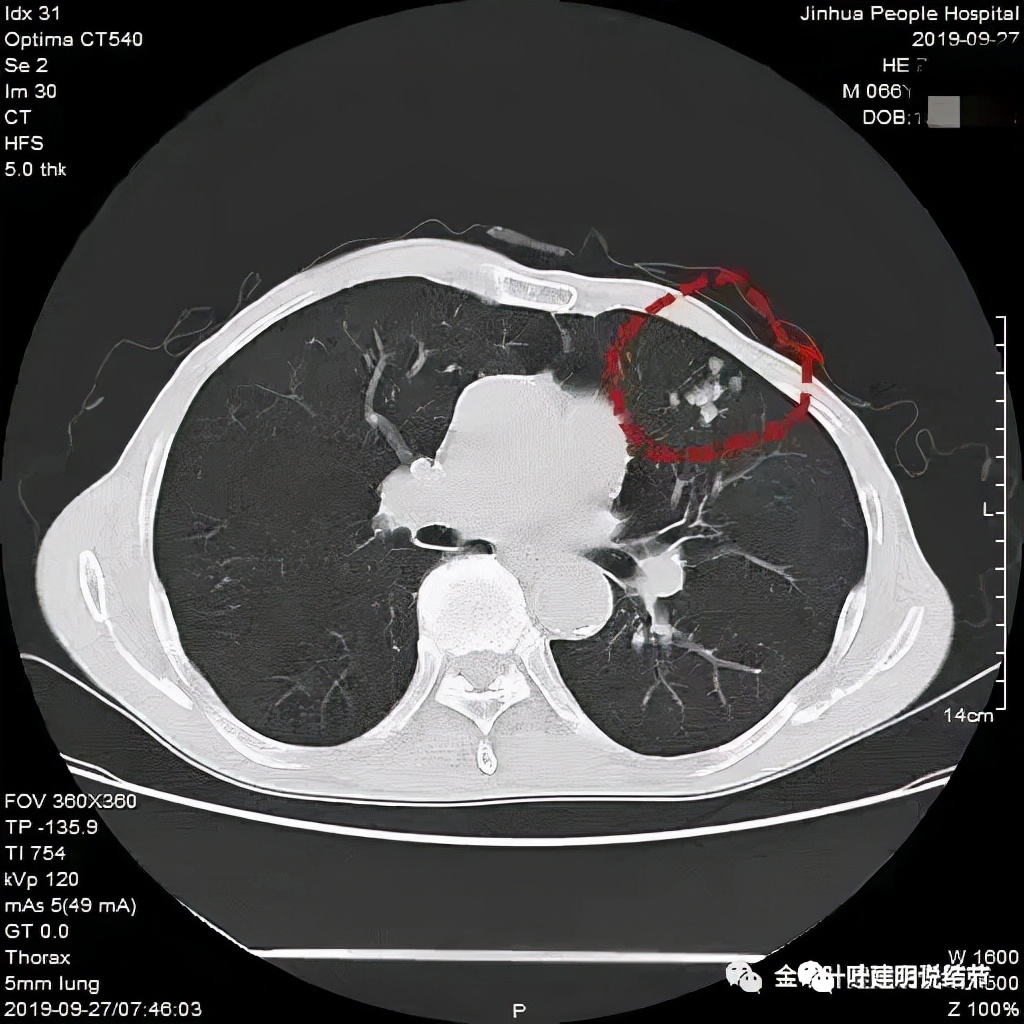

上图示病灶在左下叶,红色所指的与绿色箭头所指的是两个病灶,不相连的,实性结节

上图也示病灶是两个的,小的与大的之间有间隙的。大的病灶呈长方形似的

上图见主病灶长方形,边缘平直且光滑,没有毛刺、分叶或胸膜牵拉,粉色箭头示小病灶,在主病灶边上

上图示主病灶边缘非常光滑,膨胀性不明显

上图似乎边缘有点磨玻璃,但这可能是病灶横断面扫到组织相对较少或较薄的地方,其实并不是磨玻璃成分